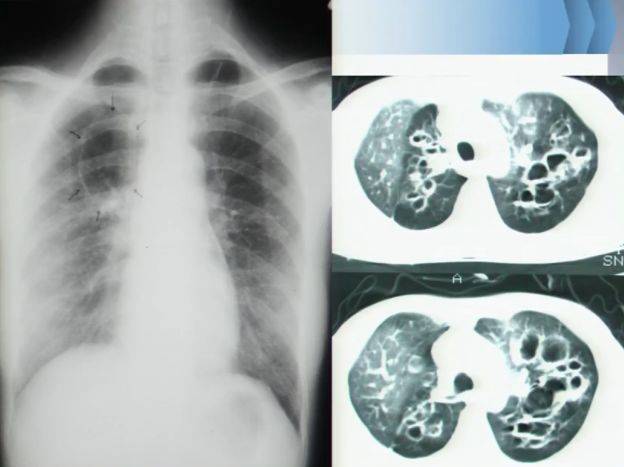

肺部常见疾病的影像诊断

肺部ct影像征象图解

呼吸影像手把手第3期|正常肺部vs基本病变影像全方位对比